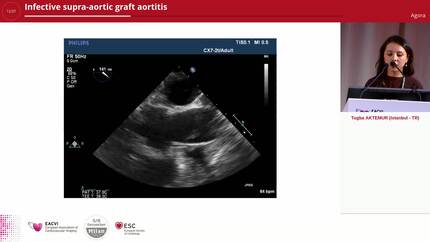

Infective supra-aortic graft aortitis